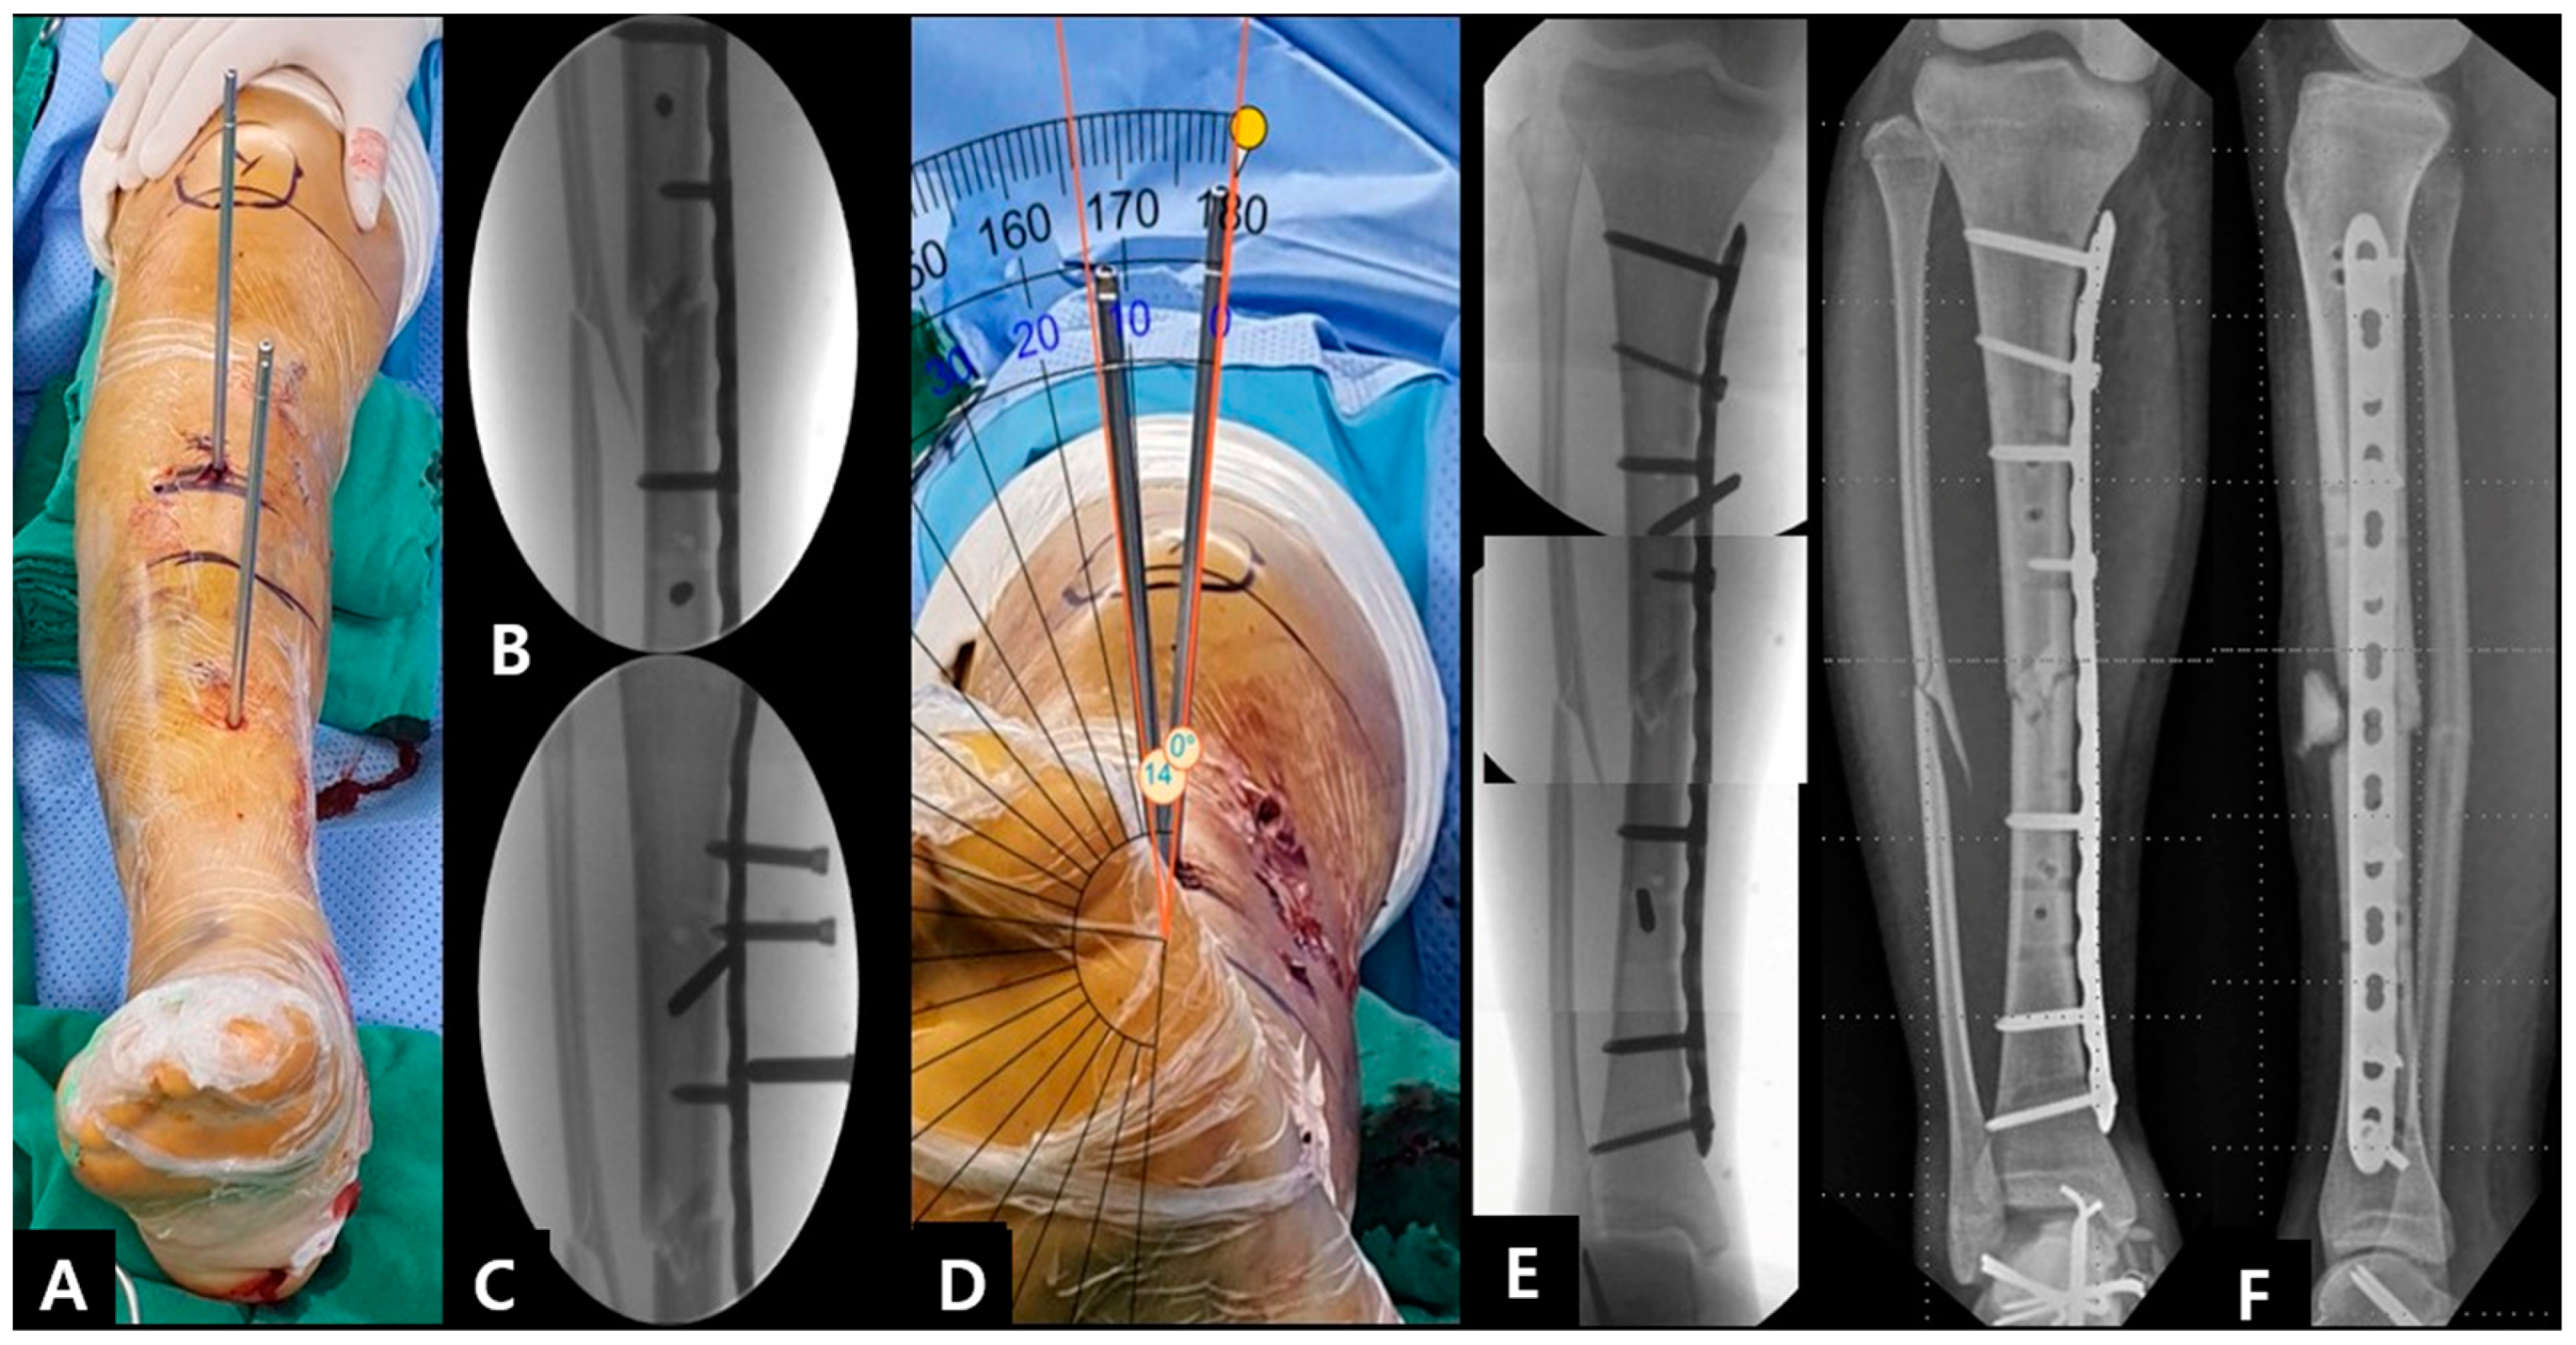

2.1. Surgical Technique

2.2. Smart Phone Application